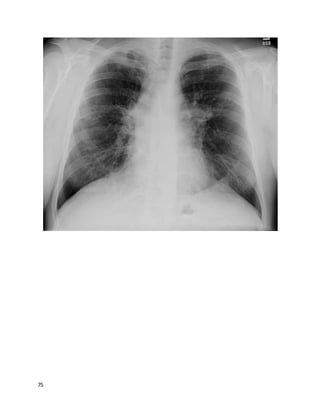

This 78 year old white woman has been coughing for "a good while"; you estimate

at least many months by her history. She is persistently fatigued, has lost 5 pounds,

but has no fevers or night sweats. She is a never-smoker. She sometimes coughs up

blood-streaked sputum. She lives in a high-rise retirement home. Other cuts of her

chest CT are similar to the one below, correlating well with the findings on chest

This is a mycobacterium avium complex infection, with Lady Windemere

syndrome (bronchiectasis and multiple small nodules often involving the right

middle lobe or lingula in nonsmoking elderly women, often with chest wall or

skeletal deformities). The other options are possible but the pattern on imaging

along with the history are most suggestive of MAC, an endemic organism inhaled

5

from soil or water. Her bronchiectasis could perpetuate her cough and hemoptysis;

however, she also has many nodules that are indicative of ongoing infection as the

primary process.Nontuberculous mycobacteria (NTM) also include M. kansasii,

rapidly growing mycobacteria (RGM), and numerous less common species.